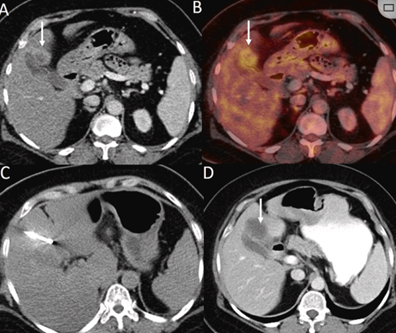

膽囊附近轉(zhuǎn)移灶(來自子宮頸癌)的冷凍消融術(shù)(A)門靜脈期 CT 圖像顯示膽囊附近有病變(箭頭)。(C) 手術(shù)過程中CT 顯示冷凍探針位于病灶內(nèi)。(D)消融手術(shù)后 1 個(gè)月CT 顯示完全消融。

(a) 射頻消融后在病變邊緣顯示殘余增強(qiáng)。(b) 冷凍消融術(shù)中影像顯示冰球完全覆蓋病變。(c) 19個(gè)月后隨訪,沒有發(fā)生局部腫瘤進(jìn)展。完全消融率為97%(66/68);2名患者均接受了額外的冷凍消融,隨后實(shí)現(xiàn)完全消融。平均隨訪期為 12.8 個(gè)月(范圍:3-27 個(gè)月)。所有患者均接受影像復(fù)查(CT 或 MRI)。11個(gè)病灶(16.2%)檢測到局部腫瘤進(jìn)展,6、12和18個(gè)月時(shí)的累積局部腫瘤進(jìn)展率分別為4%、8.2%和20.5%。8例出現(xiàn)遠(yuǎn)處肝內(nèi)或肝外病變的患者接受經(jīng)動(dòng)脈化療栓塞、經(jīng)動(dòng)脈化療栓塞加射頻消融治療或全身化療。